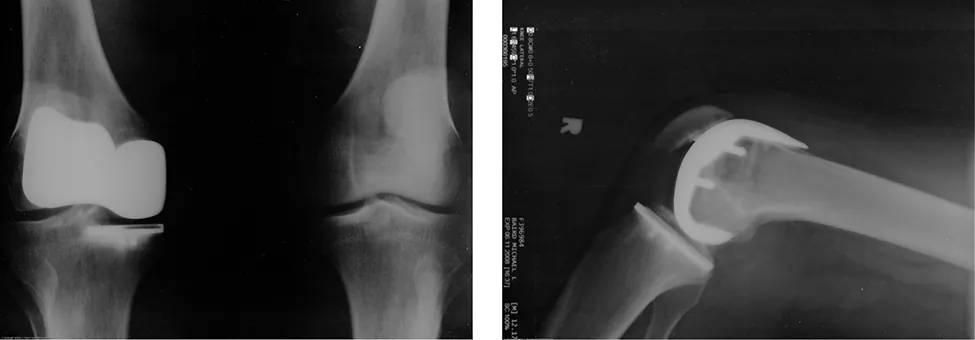

Muchas personas han experimentado lo resbaladizo que resulta caminar sobre el hielo. Sin embargo, muchas partes del cuerpo, especialmente las articulaciones, tienen coeficientes de fricción mucho menores, a menudo tres o cuatro veces menos que el hielo. Una articulación está formada por los extremos de dos huesos, que están unidos por tejidos gruesos. La articulación de la rodilla está formada por el hueso de la parte inferior de la pierna (la tibia) y el hueso del muslo (el fémur). La cadera es una articulación de rótula (en el extremo del fémur) y cavidad (parte de la pelvis). Los extremos de los huesos de la articulación están cubiertos por cartílago, que proporciona una superficie lisa, casi cristalina. Las articulaciones también producen un líquido (líquido sinovial) que reduce la fricción y el desgaste. Una articulación dañada o artrítica puede reemplazarse con una articulación artificial (Figura 6.12). Estas prótesis pueden ser de metal (acero inoxidable o titanio) o de plástico (polietileno), también con coeficientes de fricción muy pequeños.

Dos imágenes de rayos X de prótesis de rodilla artificial.

Figura 6.12 El reemplazo de rodilla artificial es un procedimiento que se realiza desde hace más de 20 años. Estas radiografías postoperatorias muestran el reemplazo de la articulación de la rodilla derecha (créditos: modificación del trabajo de Mike Baird).